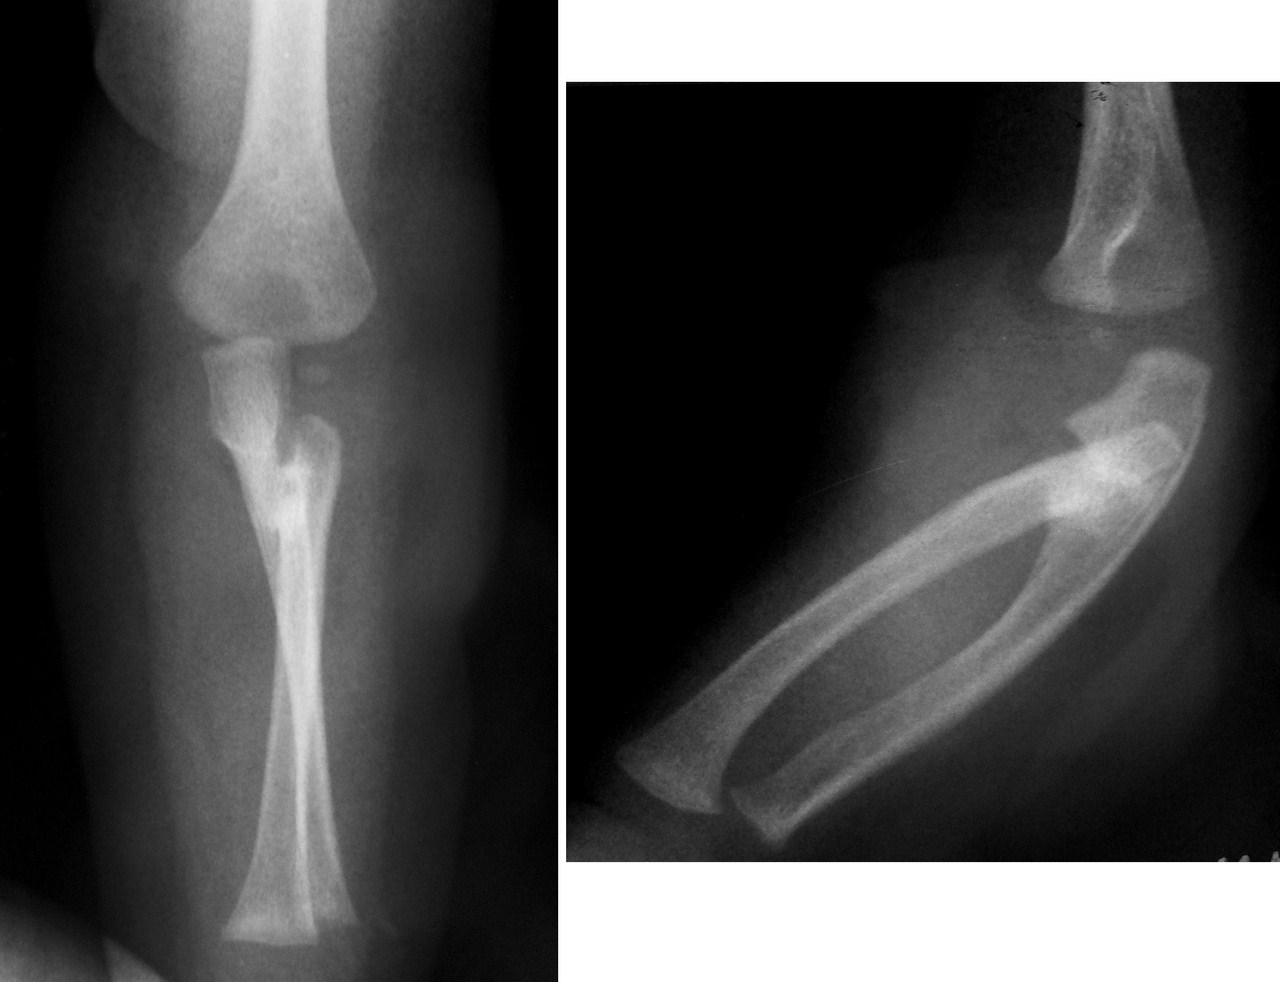

На практике чаще всего сращение наблюдается между костями голени, предплечья и сегментами позвоночника. Блокировка отдельных позвонков возникает из-за окостенения связок, вызванного краевыми переломами, вывихами или подвывихами. Локтевой и лучевой синостоз развиваются в результате сближения поврежденных костей в проблемной области, что также может происходить при вовлечении малоберцовой и большеберцовой костей.

Синостоз костей предплечья или радиоульнарный синостоз – врожденное патологическое сращение локтевой и лучевой кости. Может образовываться на любом участке предплечья, однако чаще всего выявляются синостозы в проксимальном отделе. Длина участка сращения может варьировать от 1 до 12 см.

Посттравматический синостоз — это сращение расположенных рядом костей вследствие повреждения костной ткани, эпифизарного хряща или надкостницы. Чаще всего выявляется синостоз между костями голени, костями предплечья и соседними позвонками.